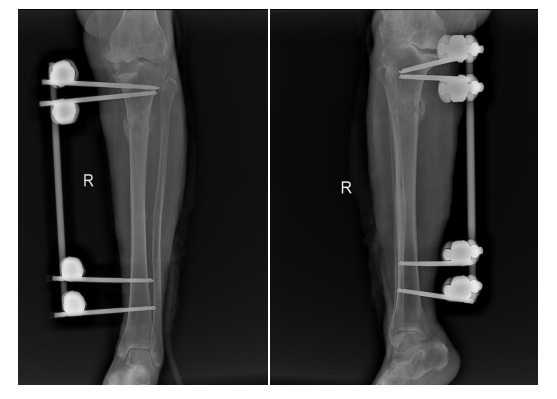

何国军主任知晓病情后,立即组织科室全体医生展开讨论,最终一致认为右胫骨骨髓炎伴胫骨病理性骨折,保守治疗效果欠佳,有手术指征。针对该病手术治疗方案主要包括:Ilizarov 技术、带血管蒂骨移植技术、Masquelet技术等,但患者术前检查提示病灶范围广,术中清创后骨缺损较大,遂制定了以负压封闭引流联合Masquelet技术为主的“三步走”治疗方案。经过充分的准备后,于2022年8月实施第一步治疗方案:骨感染、坏死彻底清创+负压封闭引流+及病理性骨折外支架固定术。

为什么负压引流【前沿技术】负压封闭引流联合Masquelet技术治疗“不死癌症”——骨髓炎_https://www.jmylbn.com_新闻资讯_第5张